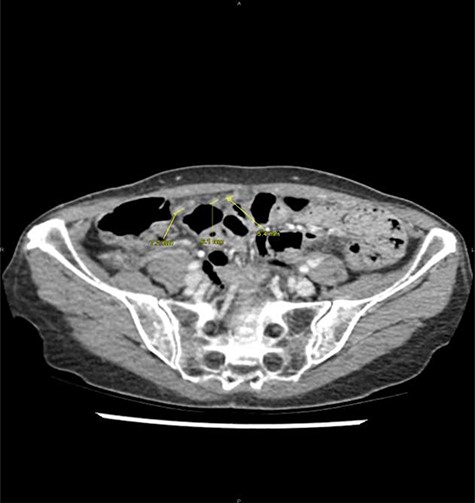

At clinical examination, abdominal pain was localized at the McBurney area, without signs of peritonitis; intestinal transit was preserved. Laboratory results showed a C-reactive protein at 2.1 mg/dl (N<1), white blood cells at 15 000 μl/m3 (N<10 000) and no liver or renal function tests alteration. On abdominal CT, a dilated appendix (12 mm) was observed with wall thickening and periappendiceal fluid, suggesting acute appendicitis (Fig. 1). An emergency appendicectomy was therefore indicated. At laparoscopic exploration, an inflamed appendix was observed as well as multiple and unexplained nodules, including an indurated lesion on the appendix. Appendicectomy was performed by ligation of the appendicular basis, and some peritoneal nodules were harvested. The postoperative course was uneventful.

Acute appendicitis on abdominal computed tomodensitometry (yellow arrow), characterized hereby by a dilatation of the appendicular lumen (12 mm) with wall thickening.